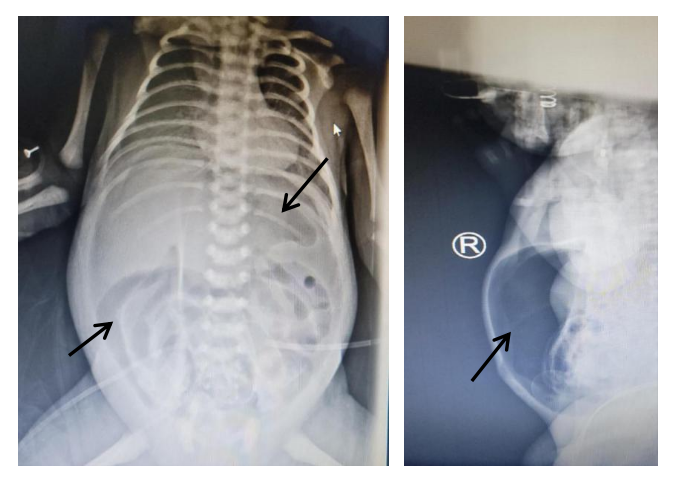

患儿术前立位腹平片

(黑色箭头为穿孔后腹部游离气体)